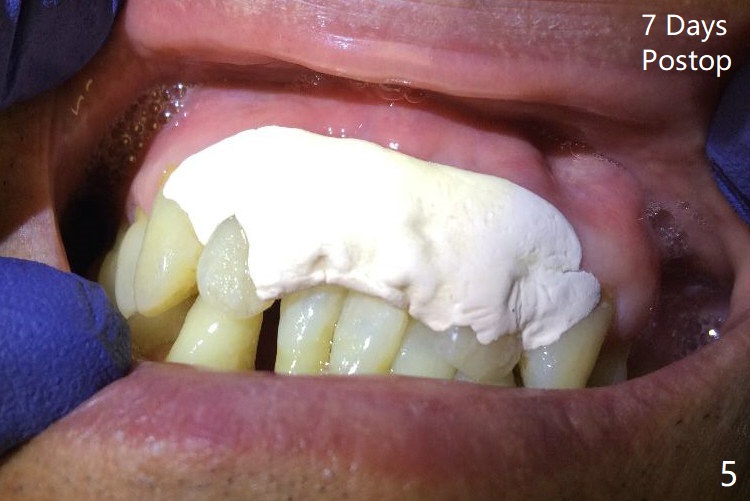

There is no buccal plate at #8 or 9 when the teeth are extracted as well as severe soft tissue defect at #8. Osteotomy is initiated as palatal as possible (Fig.1). When 3.5x13 mm implants are placed initially, the one at #8 is supracrestal (Fig.2 ^). To reduce the chance of peri-implantitis, the implant is placed deeper (Fig.3 (~2 mm implant threads exposed buccally)) with placement of sticky bone around the implants and 4.5x5.5(4) mm abutments (Fig.3 *). The buccal soft tissue defect #8 is repaired with a piece of PRF membrane (Fig.4 *), followed by periodontal dressing. Smaller 2-piece implants (3 mm, IBS) with smaller abutments (4 mm) may further reduce chance of periimplantitis and easy buccopalatal reduction of the abutments for restoration. The periodontal dressing remains stable 7 days postop (Fig.5) because it wraps around the abutments (Fig.6 A). By the time the periodontal dressing gets loose, #8 buccal soft tissue defect should be healing. When breaking-down periodontal dressing is removed 17 days postop, the coronal abutments and bone graft are exposed; after fabrication of provisional crowns (Fig.7), periodontal dressing is re-applied buccally. When the second dressing dislodges 5 weeks postop, the buccal soft tissue appears to reduce (Fig.8). Raising flaps may be less traumatic. A piece of bone graft is being extruded 4 months postop (Fig.9 >). After the abutments change from 4.5x5.5(4) to 4.5x7(3) mm, new temporary crowns are fabricated (Fig.10 (4.5 months postop)). CT shows apparent buccal bone at #8 and 9 (Fig.11,12). How to improve cosmetic?